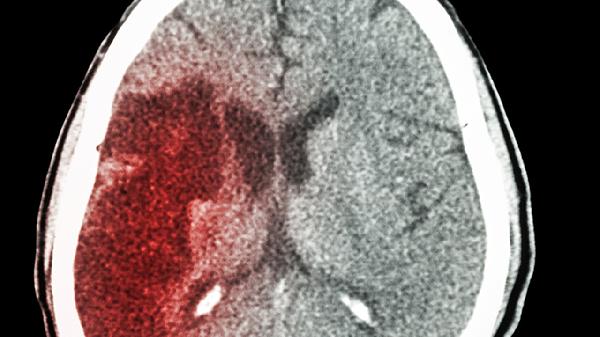

脑出血患者视力下降可能与视神经受压、视网膜缺血、颅内压增高、枕叶出血、继发性青光眼等因素有关。脑出血后血液积聚可能压迫视觉传导结构或影响视网膜供血,导致视力模糊、视野缺损甚至失明。

脑出血后血肿可能直接损伤视神经或视交叉。基底节区或鞍区出血易压迫视神经通路,表现为单侧或双侧视力骤降。需通过头颅CT或MRI明确出血部位,紧急处理包括降低颅内压的甘露醇注射液、呋塞米注射液等脱水治疗,必要时行血肿清除术。

大量脑出血会引起颅内压急剧升高,导致视乳头水肿和视神经鞘膜受压。患者出现视物模糊伴头痛呕吐,眼底检查显示视盘边界模糊。治疗需联合使用甘露醇注射液与甘油果糖氯化钠注射液脱水,监测生命体征变化。